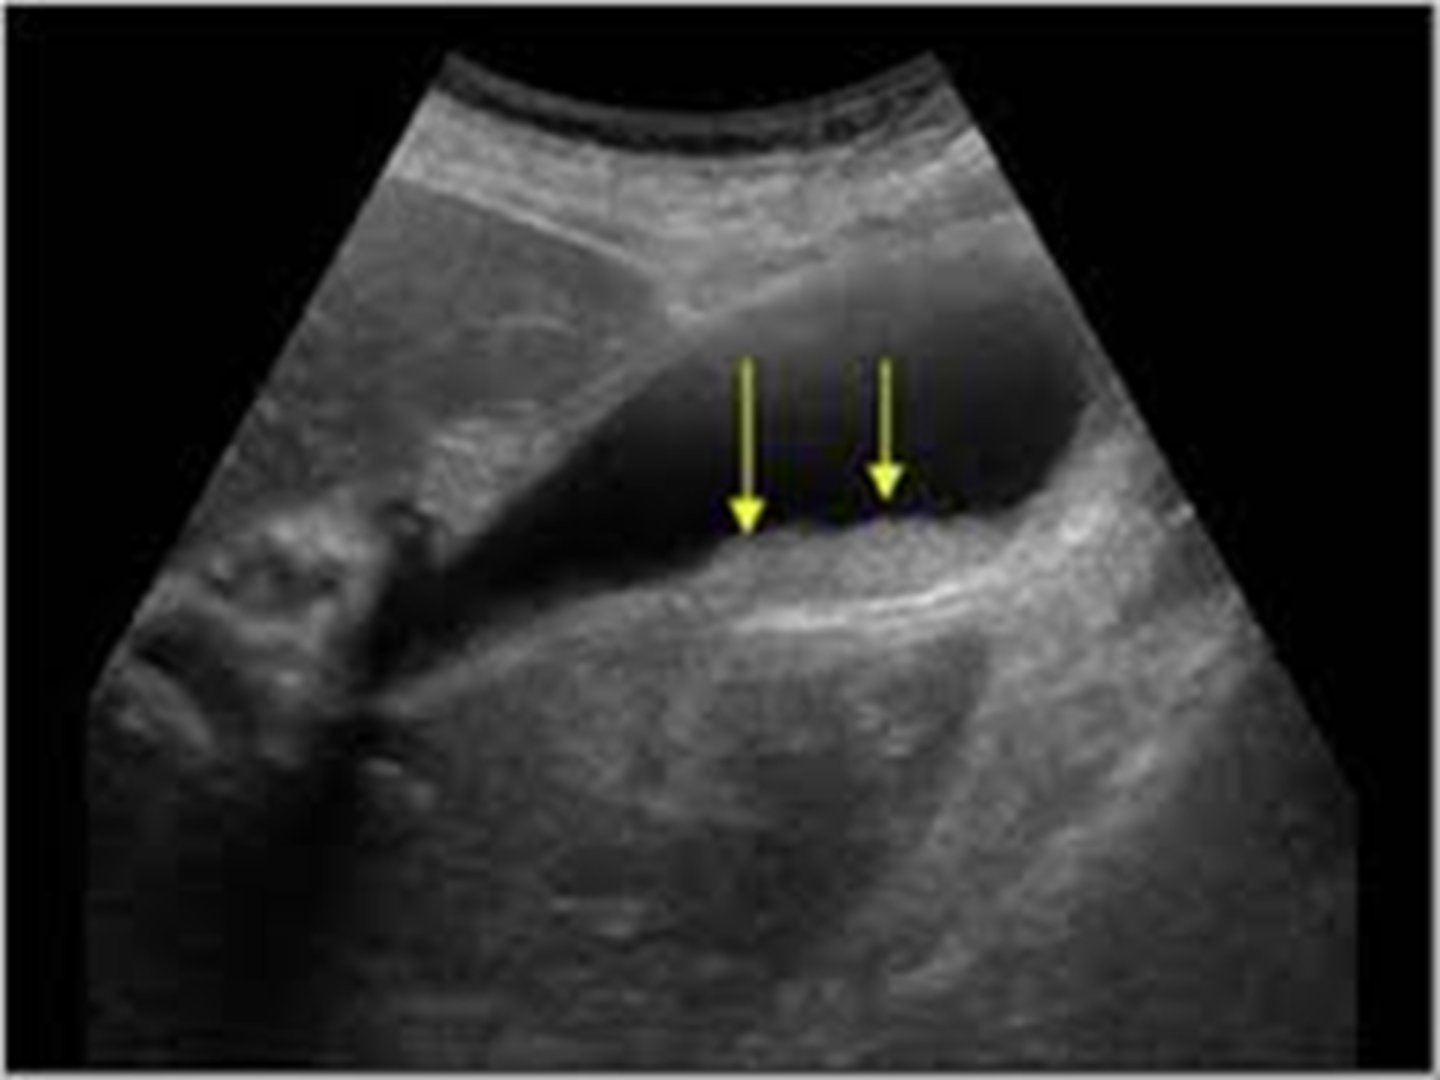

cholecystitis

inflammation of the gallbladder, usually caused by gallstone blocking outflow of bile through bile duct

-cystic duct most commonly obstructed

cholecystitis imaging

US- used most commonly, not best option

HIDA scan- useful for obstructed biliary duct, 96% sensitivity 90% specificity

MRI- 88% sensitivity 89% specificity

CT- may show perf or gangrene